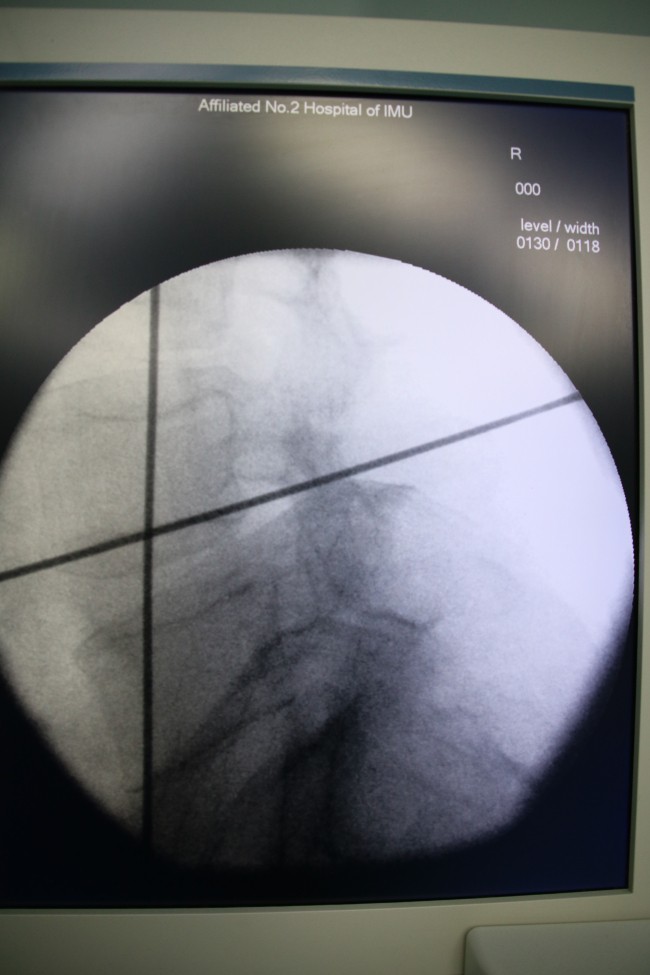

近日,我院微创脊柱外科成功为一名“腰椎不稳定继发腰椎管狭窄症”的59岁女性患者实施“OLIF”手术,为患者解除腰痛顽疾。

近年来,随着脊柱微创理念的更新以及微创技术不断发展,“靶点”治疗得到广大医学同道及患者的高度认可,常规脊柱手术逐步微创化、可视化、有限化及智能化。而OLIF(即斜外侧入路椎体间融合内固定术)治疗腰椎不稳定正是其中之代表。此项技术仅使用于腰椎不稳定伴或不伴轻度椎管狭窄,以及椎间盘源性痛的患者。此例手术皮肤切口约4cm,经腹膜外、腰大肌前缘入路,术中出血量仅为25mL。因其术中出血少,不干扰椎管内结构,对腰大肌及腰背肌无影响,无需引流,术后72小时即可下地活动,并发症发生率低,术后恢复快,住院时间短,治疗费用低,患者易于接受。